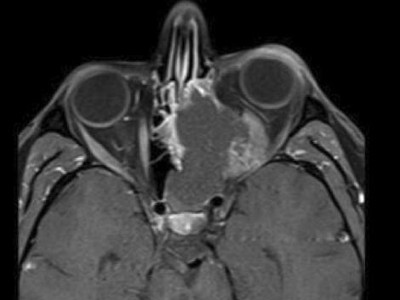

Was drückt hier auf das Auge?

Bei einer einseitigen Verschattung der Nasennebenhöhlen kommen zahlreiche benigne und maligne Differenzialdiagnosen in Frage. Oft ergibt erst die Histologie die richtige Diagnose, wie in diesem Fall eines 32-Jährigen mit rezidivierender Epistaxis, Rhinorrhoe und Druckgefühl auf dem linken Auge.

Chondroblastom in der MRT/© Camp L et al. / all rights reserved Springer Medizin Verlag GmbH, Patellafraktur/© K. Fehske · R. Hoffmann / all rights reserved Springer Medizin Verlag GmbH, Röntgenaufnahme eines nicht ossifizierenden Fibroms /© Weber M et al. / all rights reserved Springer Medizin Verlag GmbH, Cholesterolgranulom im MRT/© Frederik F/ all rights reserved Springer Medizin Verlag GmbH, pathologische distale Femurfraktur/© Omar M et al. / all rights reserved Springer Medizin Verlag GmbH, Frau unkenntlich fasst sich ans Knie/© Pornpak Khunatorn / Getty Images / iStock (Symbolbild mit Fotomodell), Echondrom/© Springer Medizin, Ausprägungen einer antiresorptivaassoziierten Kiefernekrose (AR-ONJ)/© Ristow, O. et al. / all rights reserved Springer Medizin Verlag GmbH, Stereotaktische Strahlentherapie (SBRT) einer solitären ossären Metastase in dem Brustwirbelkörper/© Springer Medizin Verlag GmbH, Arzt oder Pfleger schaut auf eine im MRT Eingang liegende Person/© [M] oksanazahray / stock.adobe.com (Symbolbild mit Fotomodell), Wirbelsäulenmetastase/© stockdevil / stock.adobe.com, Bluttransfusion/© Tobilander / Fotolia, Ärztin und kleines Mädchen mit Kopftuch/© FatCamera / Getty Images / iStock (Symbolbild mit Fotomodellen), Inhalt eines Fläschchens wird aufgezogen/© MarianVejcik / Getty Images / iStock, aneurysmatische Knochenzyste im Bereich des rechten distalen Femurs/© Springer Nature / all rights reserved Springer Medizin Verlag GmbH, Ewing-Sarkom/© Botos B. Z. et al. / all rights reserved Springer Medizin Verlag GmbH, Tumorkalzinose in der Hüfte/© Sukun A & Weber M.-A. , Computertomografie-gesteuerte periradikuläre Therapie auf Höhe von Lendenwirbelkörper 5/Sakralwirbelkörper 1 rechts/© Institut für Diagnostische und Interventionelle Radiologie des Klinikums St. Marien Amberg, Körperstereotaxie einer Lebermetastase im Segment VIII am MR-LINAC/© Ehret, F. et al. / all rights reserved Springer Medizin Verlag GmbH, Search Icon, Arthropedia, Ärzteteam führt Hüftoperation durch/© ATRPhoto / stock.adobe.com (Symbolbild mit Fotomodell), Gebrochener Fuß im Gips/© Aleksandr Kirillov / stock.adobe.com (Symbolbild mit Fotomodell)